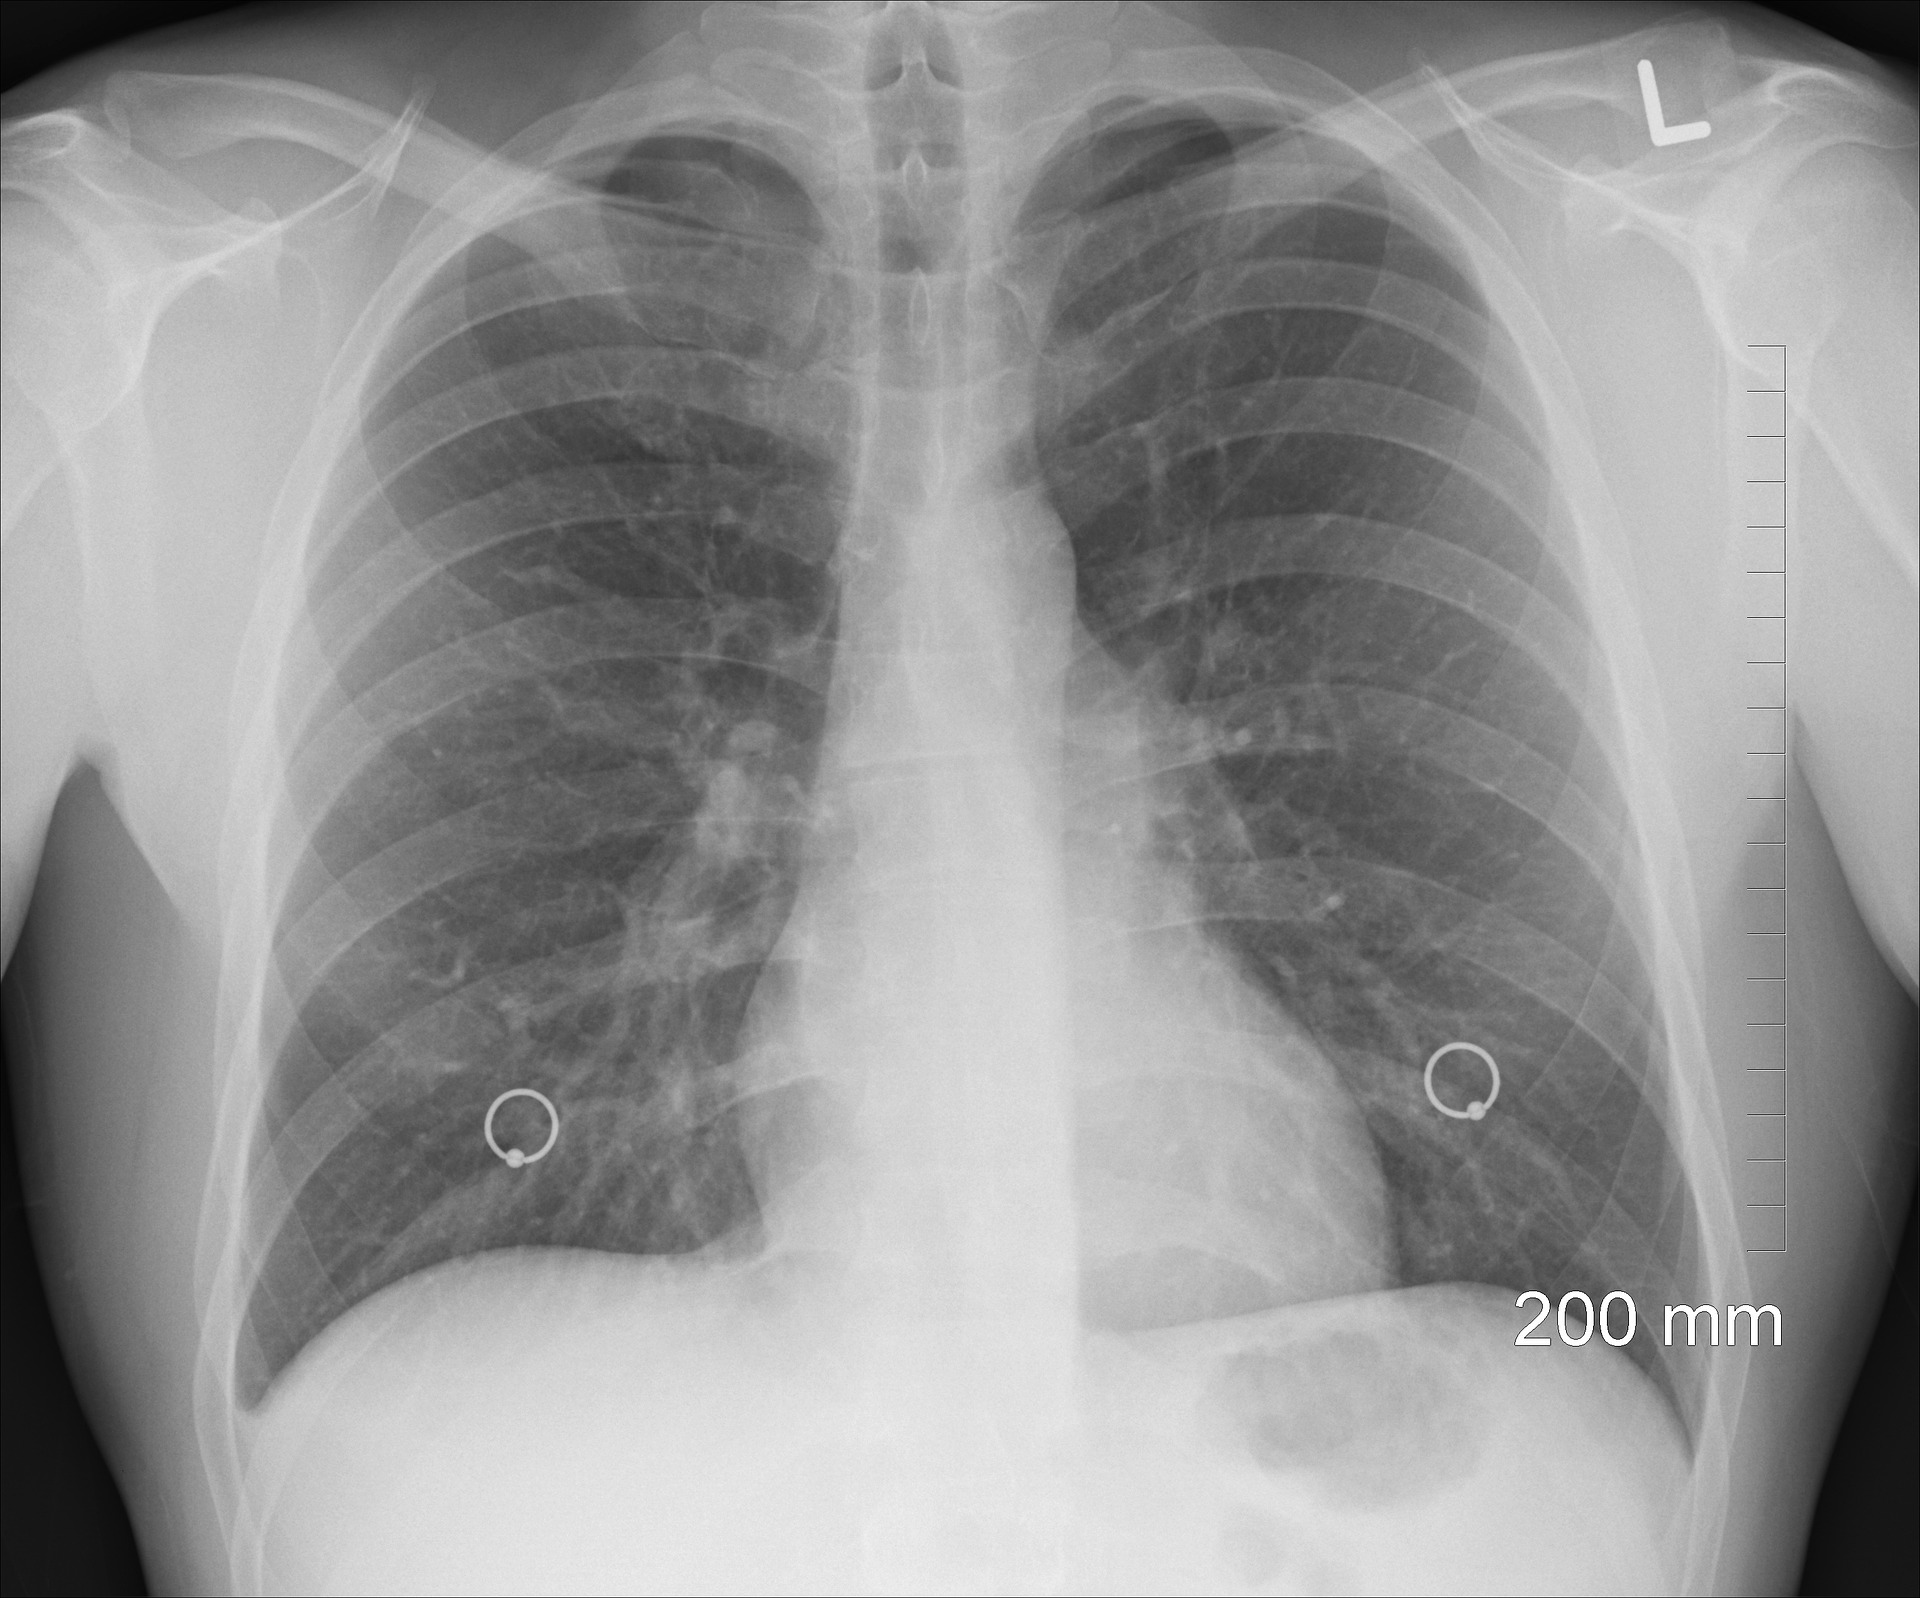

Cellular breakdown in the lungs is the greatest reason for malignant growth passing in the United States and the remainder of the world. It includes a tumor development inside the lungs, diminishing lung limit and influencing relaxing. We as of now realize that it is caused principally by cigarette smoking, however it can likewise happen because of inactive smoking or being presented to contamination or general smoke for extensive stretches of time.

The impact that cellular breakdown in the lungs has on your breathing is very noteworthy. As the tumorous mass develops, it confines the measure of air your lungs can hold – and it likewise influences encompassing vessels that get air from the lung and pass it to the remainder of the body. You'll start feeling a windedness when you just gently endeavor, and now and again, you will feel winded in any event, when plunked down and unwinding.

In extraordinary cases you will feel totally gasping for air subsequent to climbing a few steps, and here and there feel like you can't inhale by any means. As time passes by, these indications will deteriorate and more awful, making it basic that you contact your primary care physician when you start to see any side effects this way.